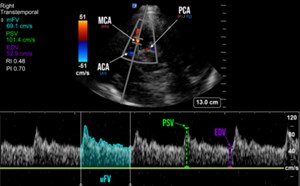

By Vivek S. Tayal, MD, FACEP and Jim Villareal, MD, FACEP The ECRI Institute, a nonprofit organization that evaluates health care technology, published a report of the “Top 10 Medical Technology Hazar...